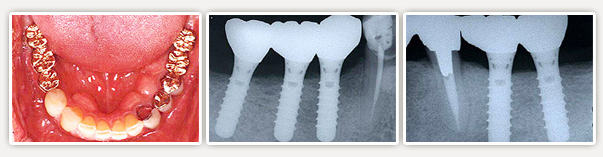

【術前】

4~5年前より左右奥歯に義歯を使われていますが、留め金が舌に触ったり、がたついて食べ物が美味しく無いそうです。また義歯そのものをつけていることが煩わしいそうです。

【術後】

左右奥をインプラントで治療しました。(左2本、右3本)